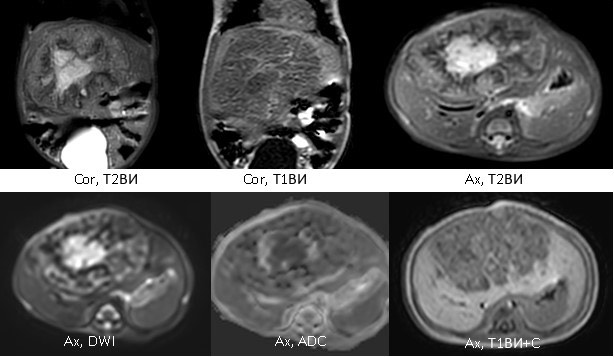

1948. Девочке 2 месяцев выполнена магнитно-резонансная томография брюшной полости с контрастным усилением, рентгенологическая картина соответствует